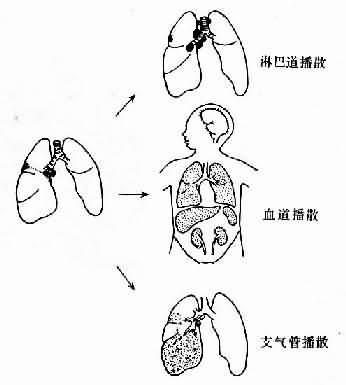

少数患儿在此时因营养不良或患其他传染病(如流感、麻疹、百日咳、白喉等),使机体抵抗力下降,病变因而恶化,肺内及肺门淋巴结病变继续扩大,并通过以下的途径播散(图18-4)。

图18-4 肺原发性结核病播散途径示意图

(1)淋巴道播散:肺门淋巴结病变恶化进展时结核杆菌可经淋巴管到达气管分叉处、气管旁、纵隔及锁骨上、下淋巴结引起病变(图18-5)。如果淋巴管因结核病变而被阻塞,结核菌则可逆流到达腹膜后及肠系膜淋巴结。预淋巴结亦可受累而肿大,此时喉头或扁桃体多有结核病灶存在。病变淋巴结肿大,出现干酪样坏死,并可互相粘连形成肿块。

(2)血道播散:结核杆菌侵入血流后经血道播散。若进入血流的菌量较少而机体的免疫力很强,则往往不致引起明显病变。如有大量细菌侵入血流,机体免疫力较弱时,则可引起血源性结核病。

(3)支气管播散:肺原发灶的干酪样坏死范围扩大,侵及相连的支气管,液化之坏死物质可通过支气管排出,形成空洞。同时,含有大量结核杆菌的液化坏死物还可沿支气管播散,引起邻近或远隔的肿组织发生多数小叶性干酪样肺炎灶。肺门淋巴结干酪样坏死亦可侵破支气管而造成支气管播散(图18-6)。但原发性肺结核病形成空洞和发生支气管播散者较少见。